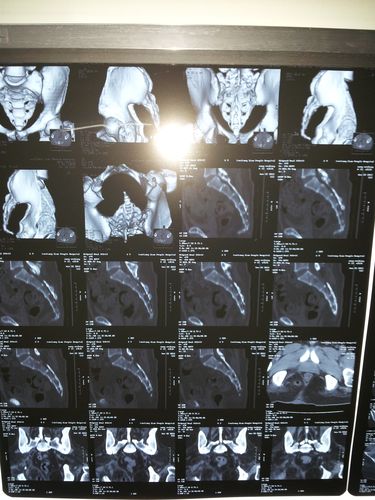

正常尾椎骨ct图,女性尾椎骨图片

问:尾椎骨受伤,这是拍的x片,请帮忙看下严不严重?

69 骨科与显微外科专业讨论版 69 【原创病例】 因"反复骶尾部

十七年前从高处跌下,尾骨严重错位,最下面一节前倾呈90度,第二节严重

尾椎骨ct图

尾椎骨ct图片

正常骶尾骨ct图片

骶尾骨骨折ct图片

骶尾骨ct图片